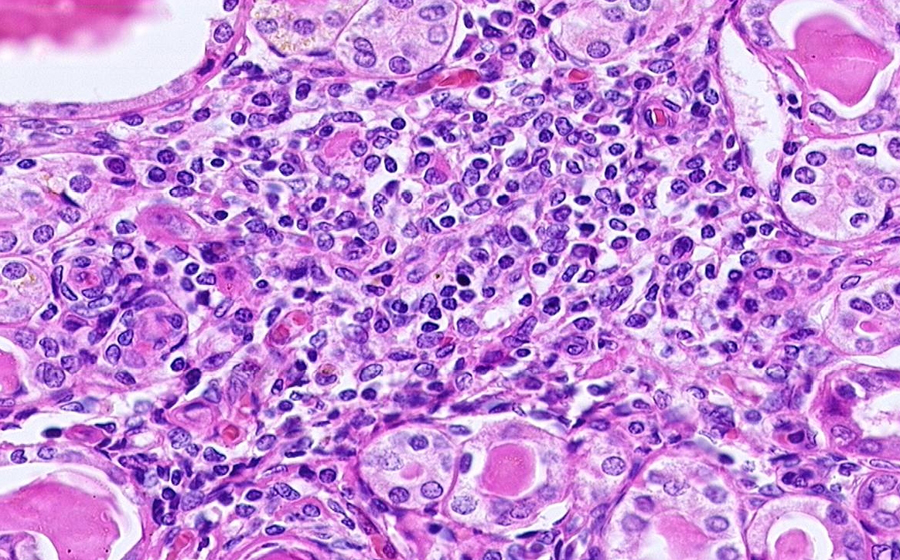

Slide 3: Glomerulonephritis - chronic

Histologic section of kidney from a patient with chronic glomerulonephritis. (click here to review normal tissue)

Image 4 - 100X

Slide 3 - Image 4